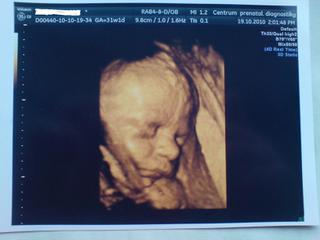

Holky tak jsme podle ultrazvuku o týden starší, tak já nevím...dnes 32+2 a máme 1900 gramů.